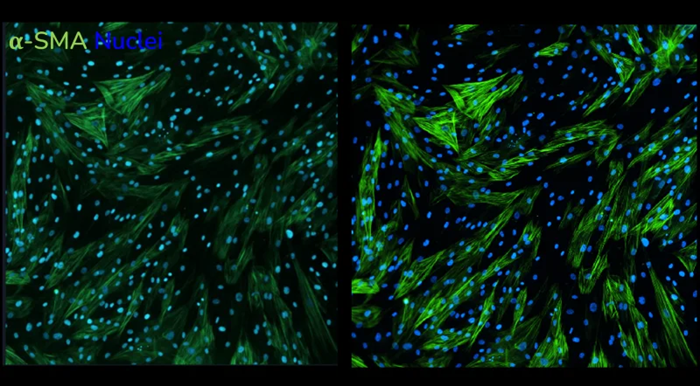

Enhanced sensitivity and rapid screening

When assessing the effectiveness of anti-fibrotic drugs, the HTHS FMT assay is extremely sensitive to detecting subtle variations in the expression of fibrotic markers. Compared to LED-based imaging, laser-based α-SMA expression imaging and quantification produces a "steeper" dose-response curve with a larger area under the curve, resulting in an assay with higher overall sensitivity.

- Compared to LED-based imaging, laser-based imaging has a higher sensitivity and can detect more subtle changes in the expression of fibrotic markers

Increased resolution of laser-based acquisition. α-SMA staining following stimulation of human lung fibroblasts with TGF-β1 captured using LED-based imaging (left) vs. laser-based imaging (right). Images taken at 20x magnification. Image Credit: Newcells Biotech